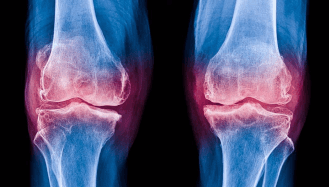

Dr Alan Cheung is an orthopaedic surgeon and the Medical Director of the International Orthopaedic Clinic in Singapore. He specialises in sports injuries, adult joint reconstruction, and minimally invasive robotic surgery. Employing evidence-based techniques for sports injury treatment, joint replacement surgery, and pain management, he aims to help patients quickly regain mobility and return to active lifestyles. Dr Cheung’s commitment to excellence is reflected in his continued contributions to orthopaedic research and innovation.

- Specialised in Sports Surgery, Joint Reconstruction & Robotic Surgery